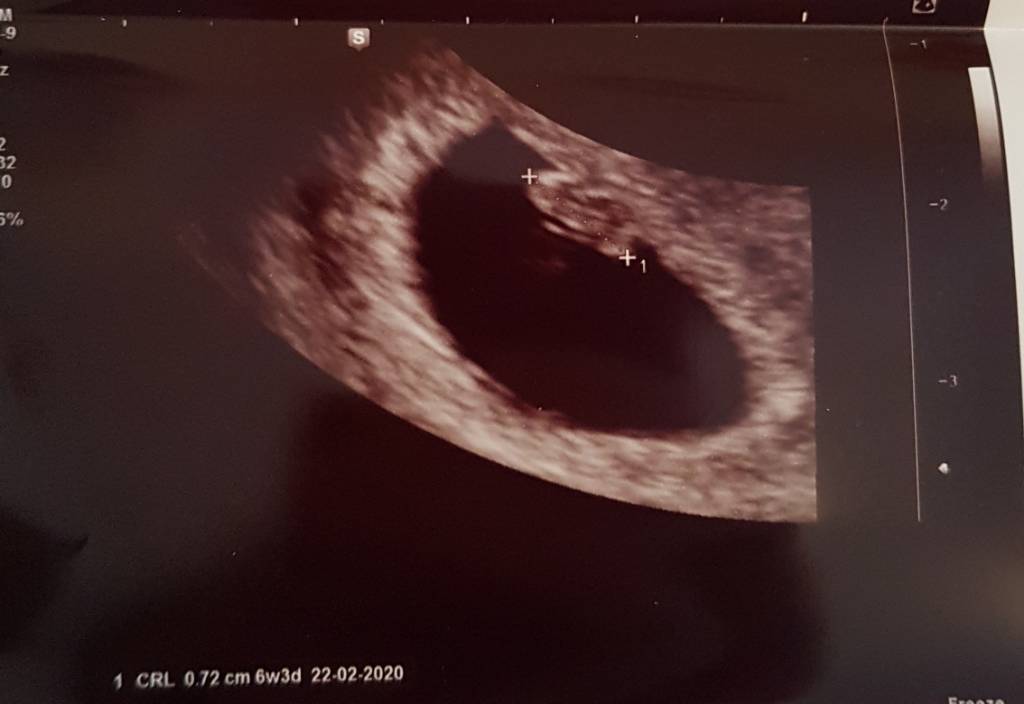

ale slodziaczekJa po wizyciewszystko ok, serduszko bije. Dzidzia ma 7mm i jedyne co to muszę pić glukoze już ze względu na cukrzycę ciążowa w pierwszej ciążyZobacz załącznik 993167

@Kasia654 piękne maleństwo. mamy w zasadzie podobne dzidziutki [emoji16] mój 7.4mm [emoji6]